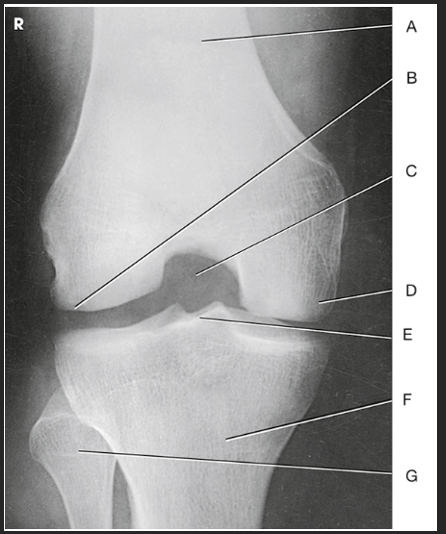

Name this projection

AP oblique medial rotation

What is demonstrated?

Lateral aspect (distal femur, patella, lateral tibial condyle, fibular head, and proximal tibiofibular joint)

What joint is demonstrated?

Proximal tibiofibular joint

Label the image: A

patella

Label the image: B

medial femoral condyle

Label the image: C

lateral femoral condyle

Label the image: D

medial tibial plateau

Label the image: E

Lateral tibial plateau

Label the image: F

medial tibial condyle

Label the image: G

lateral tibial condyle

Label the image: H

tibiofibular articulation

Label the image: I

fibula

Label the image: J

tibia